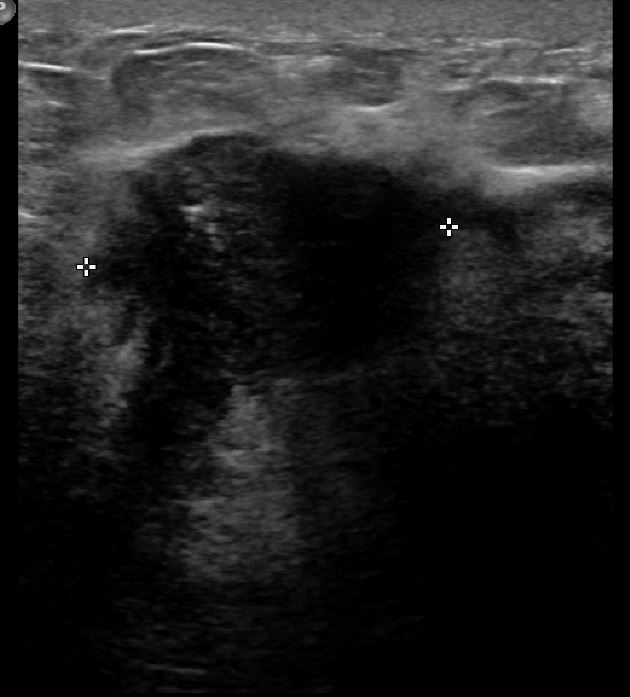

아산유외과 개원후 621번째 유방암 진단

상기 환자 외부검사상 이상소견으로 내원하신 50대 여성으로 우측에 의심스러운혹있어 조직검사 시행후 유방암 진단되었습니다.